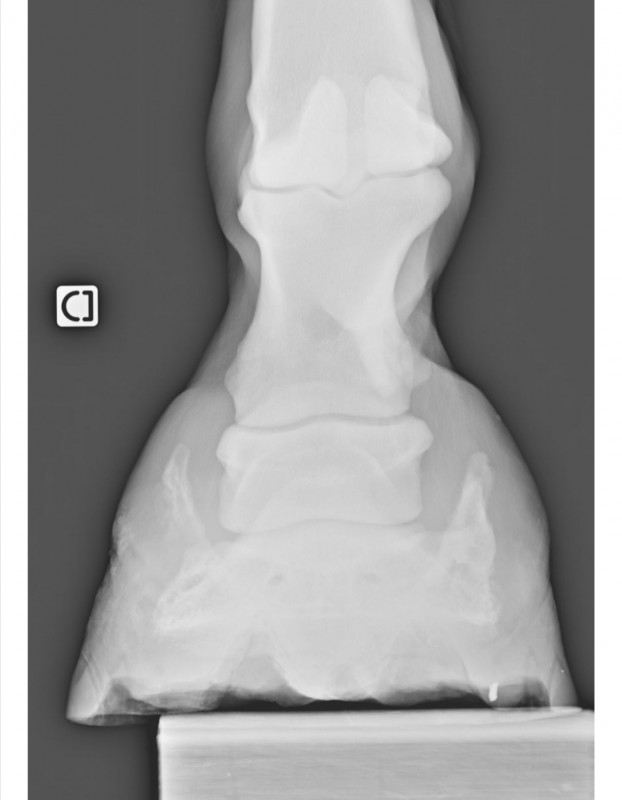

Résultat : arthrose en face antérieure de la 2ème phalange et ossification des cartilages ungulaires. D'après la véto, inutile de faire des radios de l'autre pied. Pour elle c'est sur qu'il y a la même chose, peut-être en moins développé mais présent quand même. C'est parait-il la "maladie des chevaux de trait"

marechal05 Oui j'ai fait des radios de l'antérieur droit en 2017 suite à une boiterie. La véto n'avait pas pensé nécessaire d'en faire de l'antérieur gauche qui d'après elle devait très certainement avoir les mêmes problèmes : arthrose sur la face antérieure de la 2ème phalange et ossification des cartilages ungulaires.

Antérieur droit Mars 2017

Antérieur gauche Septembre 2019